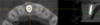

Elle présente une resorption interne importante due à un choc à l age de 9 ans.

La décision d'extraction implantation immédiate est prise avec comblement post extractionnel à l aide de xenogreffe Bio oss(c).